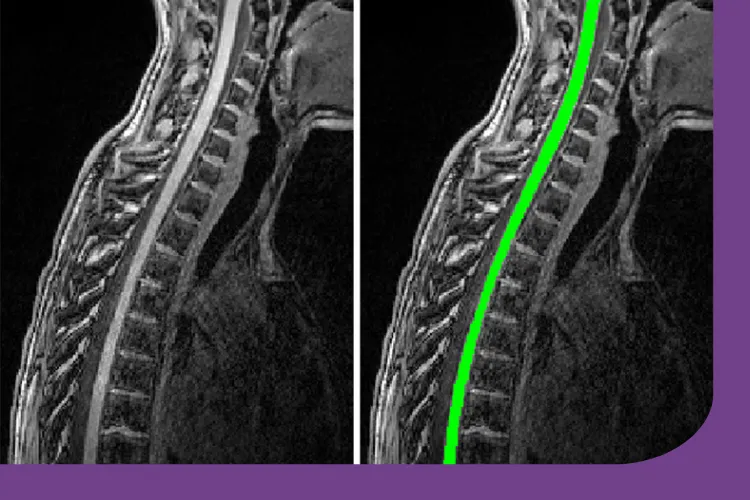

MS damages the nerves in the brain and spinal cord, which, over time, can lead to difficulties with movement and daily activities. This progresses differently for each person and unfortunately, we cannot yet predict how severe an individual's MS will become. To better understand MS and enable people to plan for the future, we need ways to better measure nerve damage. MRI scans of the brain and spinal cord can help with this.

While MS affects both the brain and spinal cord, however, most research has focused on nerve damage in the brain. We know less about how MS damages the spinal cord, even though this is closely linked to the difficulties people living with MS may experience. Additionally, most research so far has looked at the upper part of the spinal cord only, and focused on people living with MS for many years.

Now, Dr Meijboom and colleagues have been awarded funding by the MS Society to undertake a pilot (preliminary) study called CORD-MS. In this research, the team will test new and standard MRI scans along the full length of the spinal cord, in people who have recently been diagnosed with MS. The study team will start recruiting participants later this year, looking for people who were diagnosed with relapsing-remitting MS in the last six months.